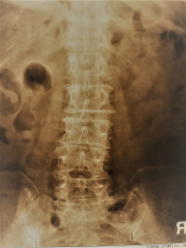

椎間板の消失 骨変形に伴う弯曲(1) (2) カルシウムの沈着

腰痛はもちろん、下肢のしびれ・筋力・感覚低下・麻痺・膝の変形などの他、排尿・排便障害に至ります。

これらのレントゲン写真のような人は程度に差はあれ、60代後半の人に多く見受けられている状態です。